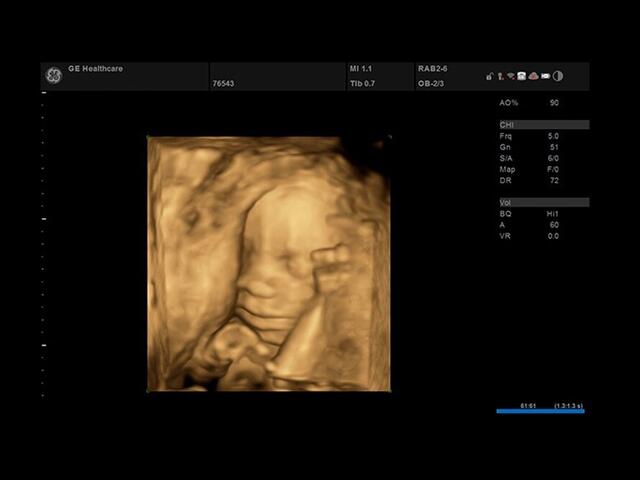

• SonoBiometry : Эта функция позволяет быстро измерить биометрические параметры плода, такие как длина бедра, окружность головы, окружность живота и длина кости. Это важно для контроля развития плода и оценки его состояния.

• VOCAL : Это 3D-инструмент, который позволяет рассчитывать объем участков эксцентрической формы или сложных анатомических структур. Он полезен при анализе и измерении объемных образований внутри органов.

• 3D/4D - Да

• Автоматичексая биометрия плода (БПР, ОГ, ОЖ, ДБ) - Да